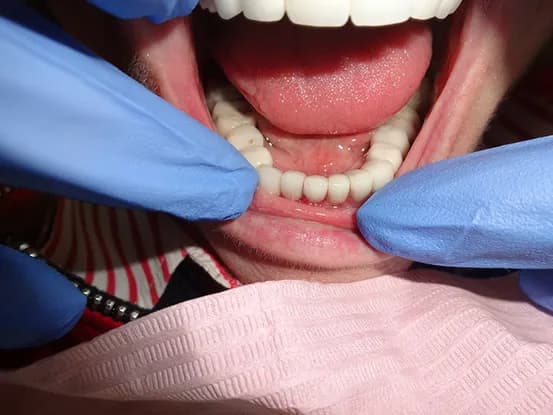

Case 4

58 year old female with unstable partial upper denture due to lack of anchor teeth on upper right quadrant. 4 implants placed and elimination of denture and improved masticatory function.